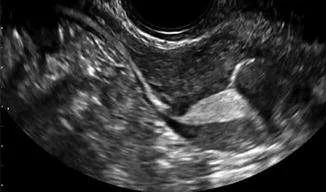

يتم عمل فحص الرحم و قنوات فالوب بحقن مادة مخصوصة للانعكاس على جهاز السونار باستخدام قسطرة رفيعة تمر من خلال عنق الرحم لحقن المادة. ثم يتم بعدها الفحص باستخدام جهاز السونار. تستخدم هذه الطريقة لان نتائجها تماثل اشعة الصبغة لكن تمتاز بعدم الحاجة الي تخدير عام او التعرض لإشعاع اكس راي. لكن تفتقر الي اعطاء معلومات عن عدم وجود التصاقات في حوض البطن.